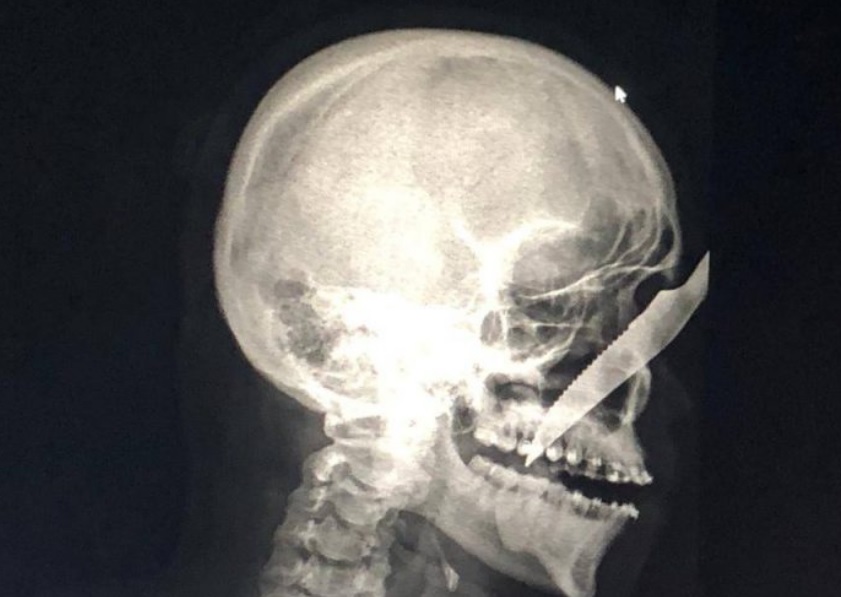

Jovem passa por cirurgia de emergência no Amazonas após levar facada de bêbado na rua

MANAUS –  Um bêbado deu uma facada em um rapaz no meio da rua em Carauari, no interior do Amazonas, e por muito pouco a vítima não perdeu a vida, dando entrada no hospital da cidade com a faca cravada no rosto  Alberto Carvalho de Oliveira, de 25 anos, foi atendido às pressas.

O agressor está detido e a vítima passa bem, mas a imagem viralizou nas redes sociais.